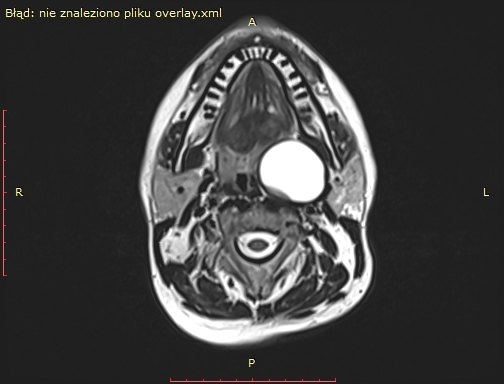

Badanie rezonansu magnetycznego wykazało (widoczne na zdjęciu) u pacjenta obecność dużej zmiany torbielowatej w przestrzeni przygardłowej po stronie lewej o wymiarach 54x42x38 mm. Zmiana miała postać torbieli zawierającej jednolity płyn, z pogrubiałą, postrzępioną wewnętrzną ścianą i gładką powierzchnią zewnętrzną. Torbiel powodowała przemieszczenie i ucisk okolicznych struktur. Biopsja aspiracyjna cienkoigłowa sugerowała torbiel boczną szyi.